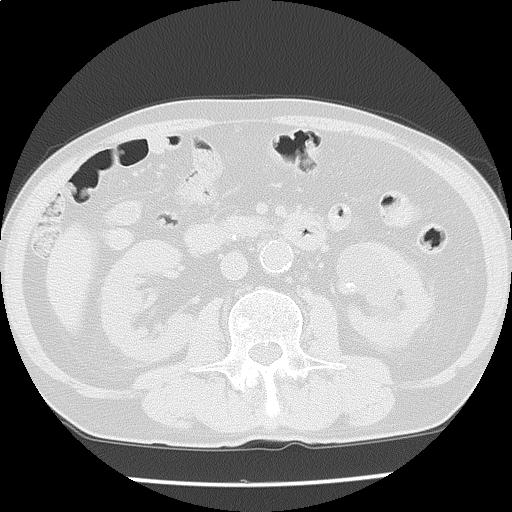

【読影指南】CT画像読影クイズ 問題1

咳が続く。甲状腺から骨盤までスクリーニング

年齢: 76歳

性別: 男性

検査部位: 胸腹部

検査種別: CT

CTスライス画像

CTスライス1

下記から正しいものを選べ